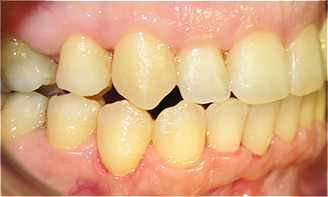

Apinhamento dentário com os dentes caninos em desoclusão (classe II, divisão 2).

![]() |

Após dois anos de tratamento ortodôntico.